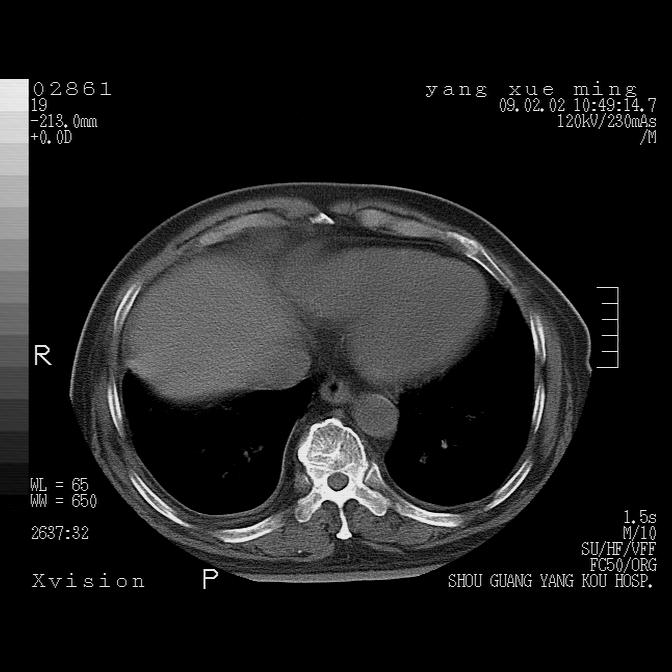

以下是引用lkc8963在2009-2-3 20:11:00的发言:[br]1)右上肺陈旧病灶。2)右下肺团块及团片影,影像表现符合感染。3)左心增大,左冠脉钙化,符合冠心病。4)双侧肺门扩大,以左侧为著,肺动脉干略粗,左上肺局限性气肿,为谨慎起见,需除肿瘤,建议增强。

以下是引用zbp537在2009-2-3 19:08:00的发言:[br]我诊断为肺泡性肺水肿。[br]诊断依据:[br]1、心影普遍增大,肺血管增粗,并见絮状高密度影,肺门改变显著。[br]2、临床上表现胸闷咳嗽,无发烧,不是一个典型的肺部感染的病史。

以下是引用王仕学在2009-2-3 20:28:00的发言:[br]考虑右下肺感染,建议治疗后复查。